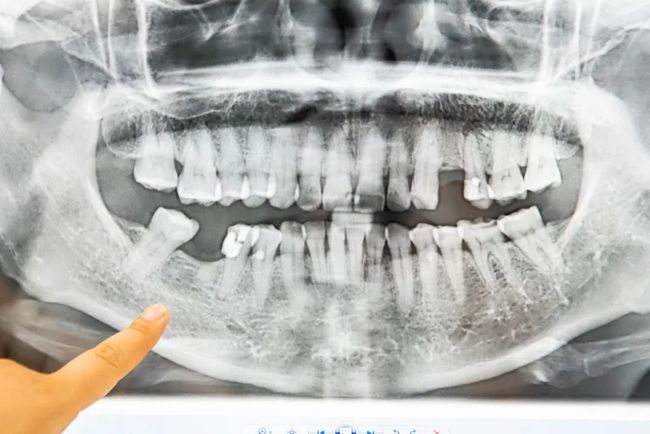

单牙缺失

种植后